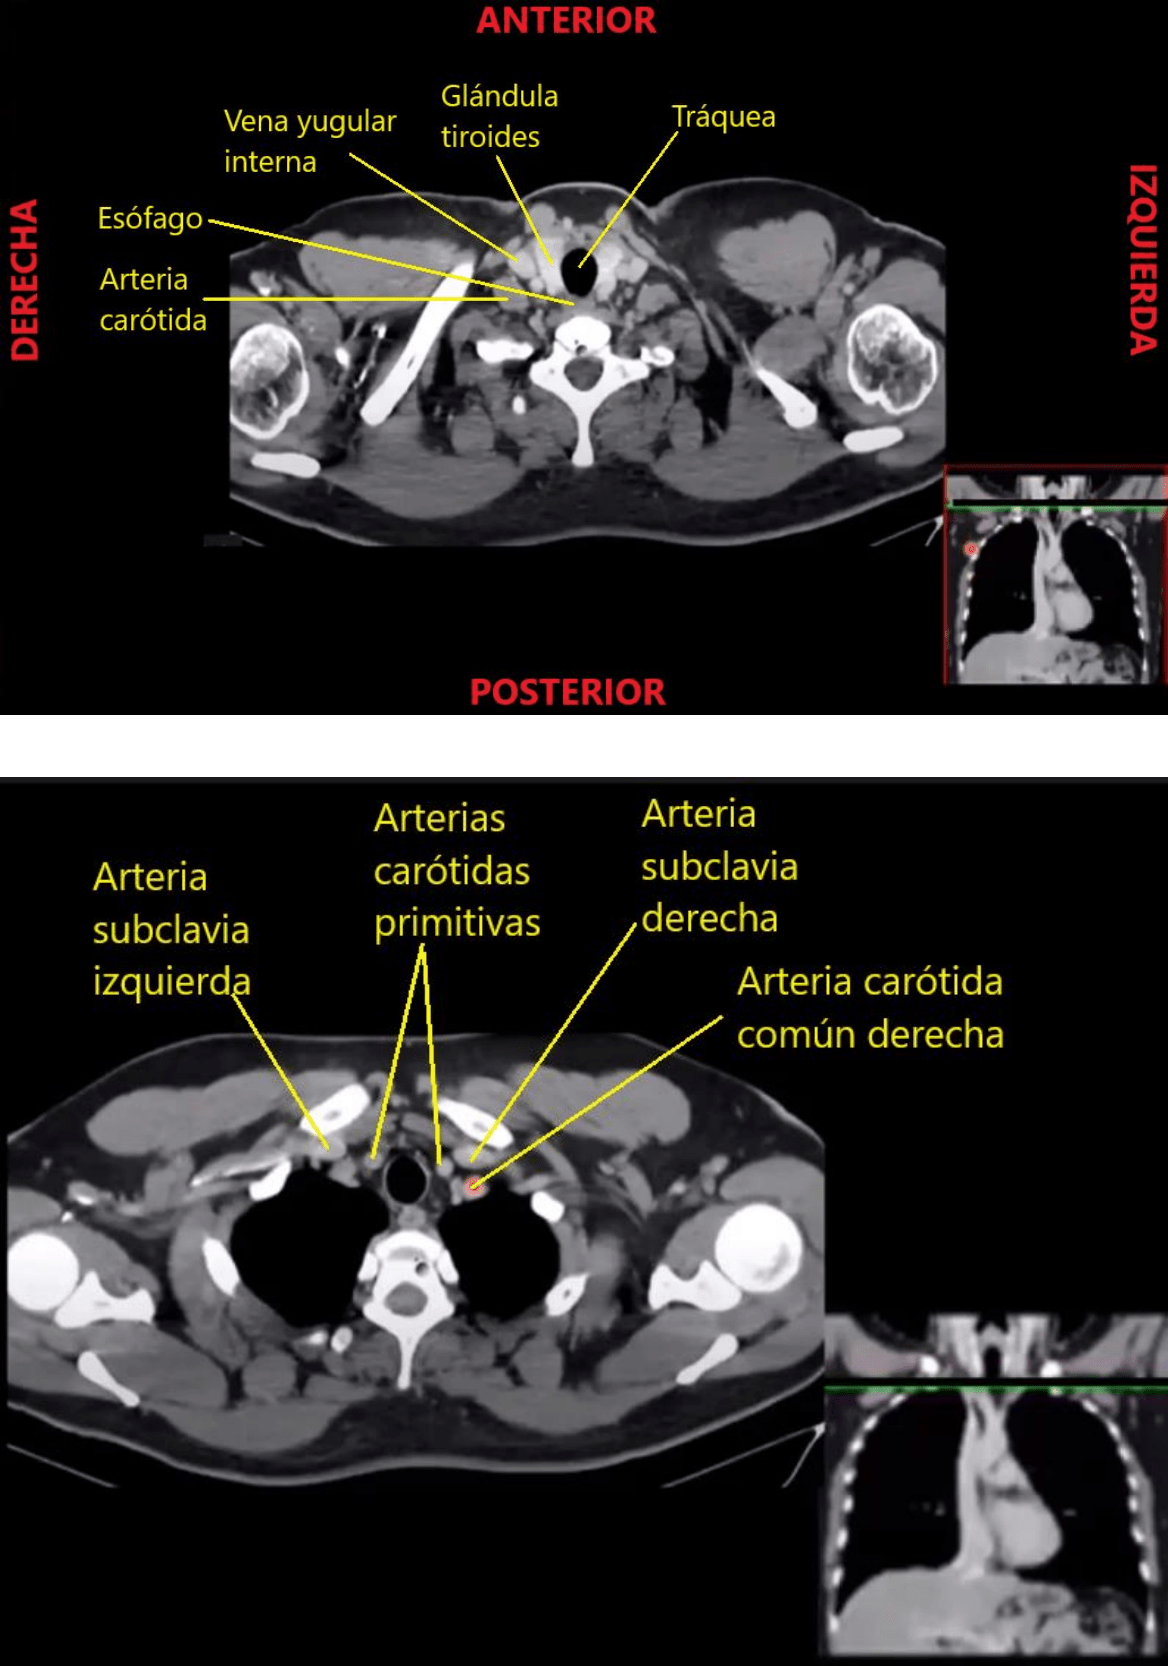

TAC de tórax, corte axial.